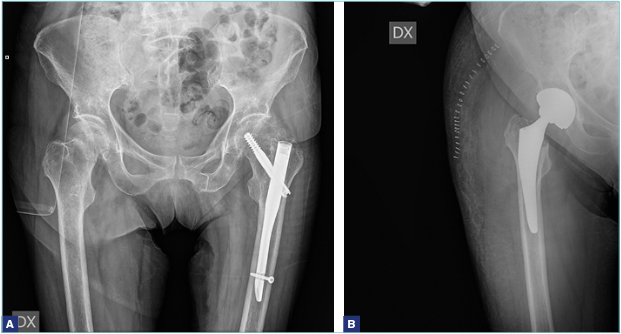

Quando invece si ricorre alla sostituzione protesica, esistono diverse soluzioni: la endoprotesi, o protesi cefalica, e l’artroprotesi. Per “endoprotesi” si intende un impianto in cui si sostituisce soltanto l’estremo prossimale del femore, senza intervenire sull’acetabolo. Per tanti anni è stato fatto uso della endoprotesi di Moore, protesi monoblocco, semplice da posizionare e poco costosa, ma la tendenza a dare usura della componente acetabolare e dolore in tempi relativamente brevi ha reso questo impianto obsoleto. Attualmente, l’impianto più usato è la protesi biarticolare, in cui la testa della protesi ruota su una componente acetabolare ancorata a essa senza fissaggio nel cotile nativo. È dimostrato che questo sistema riduce sensibilmente l’usura dell’acetabolo. L’artroprotesi totale, che consiste nella sostituzione della testa femorale e nell’impianto di una componente di rivestimento dell’acetabolo, è riservata ai pazienti più giovani in cui non è indicata la sintesi. L’obiettivo della artroprotesi è proteggere il paziente nei confronti di una possibile artrosi, che potrebbe manifestarsi nei successivi anni di vita. L’intervento di artroprotesi ha tempi chirurgici più lunghi rispetto all’endoprotesi e un maggior rischio di lussazione 7, ma è l’impianto di scelta nei pazienti meno anziani e, in caso di artrosi già presente, anche nel paziente più anziano. Negli ultimi anni è stata proposta un’artroprotesi a doppia mobilità, che ha il vantaggio di un minor rischio di lussazione.

Per quanto riguarda le fratture laterali (basicervicali, pertrocanteriche, sottotrocanteriche), l’indicazione condivisa universalmente è quella a un intervento di osteosintesi, che può essere effettuata con un chiodo-vite, rappresentato da un chiodo endomidollare che si introduce nel canale diafisario del femore e da una vite cefalica, con un angolazione variabile (si introduce nel collo del femore fino alla testa), o con una vite-placca, in cui la sintesi consiste in un sostegno laterale (la placca) più la vite cefalica, anche questa di varia angolazione. Nelle fratture sottotrocanteriche è raccomandato l’uso del chiodo endomidollare di lunghezza variabile in base alle caratteristiche e alla sede della frattura.